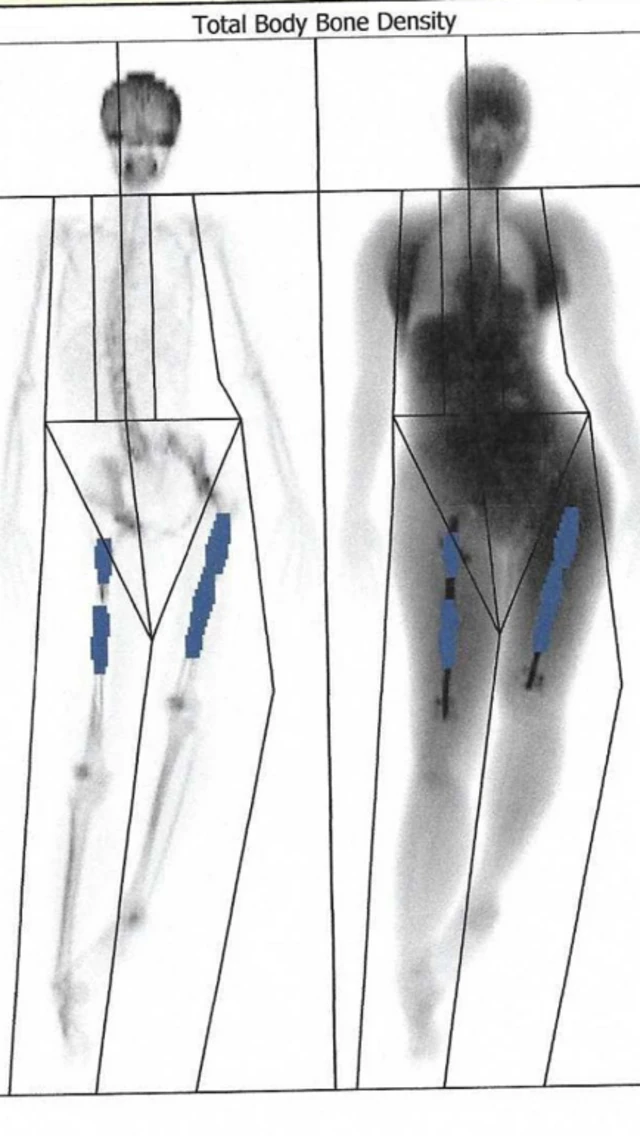

ቀዶ ህክምናው የእግር አጥንቶች ለሁለት ተሰብረው በመካከላቸው የብረት ዘንግ የሚገባበት ሂደት ከመሆኑ ጋር ተያይዞ ህመሙ የሚጠበቅ ነው።

በሁለቱ አጥንቶች መካከል የሚገቡት የብረት ዘንጎች ቀስ በቀስ እንዲራዘሙ ይደረጋል። በዚህም በሁለቱ አጥንቶች መካከል ያለውን ርቀት በማፈራቀቅ ቁመት እንዲጨምር ያደርጋሉ። ለሁለት እንዲሰበሩ የተደረጉት አጥንቶች ቀስ በቀስ ድነውም በመካከላቸው ያለው ክፍተት ተሞልቶ ወጥ ይሆናል።

የእሌይን ቀዶ ህክምና ከተጠናቀቀ በኋላ እግሯ የመራዘሙ ሂደት ተጀመረ። በየዕለቱም ምቾት የማይሰጡ ለምሳሌ እግሮቿን በማሽከርከር የገቡት የብረት ዘንጎች የሚራዘሙበትን ሂደት መሥራት አለባት።

በዚህም መንገድ ነው የገቡት የብረት ዘንጎች ተራዝመው እግሮቿን የሚያሳድጉት። ነገር ግን ከሁለት ሳምንታት በኋላ ያልጠበቀችው ቀውስ ገጠማት።

እሌይን ክሊኒኩ ሄዳ የስካን ምርመራ ተደረገላት። በግራ እግሯ ላይ ያለው አያያዥ ሚስማር ጭኑዋ ላይ ያለው አጥንት ውስጥ ተሰብሯል።

ፊመር የተሰኘው ይህ የጭን አጥንት በሰውነታችን ውስጥ ከሚገኘው ጠንካራው አጥንት ነው።

በአውሮፓውያኑ 2017 ሚያዝያ ወር ላይ የግራ እግሯን የማራዘም ሂደት እንደገና ተጀመረ። በተመሳሳይም በግራ እግሯ ላይ ያለውን አጥንቶች ተጋጥመው በወጥነት እንዲያድጉ ለማድረግም የአጥንት መቅኒ (ቦን ማሮው) በመርፌ ተወጋች።